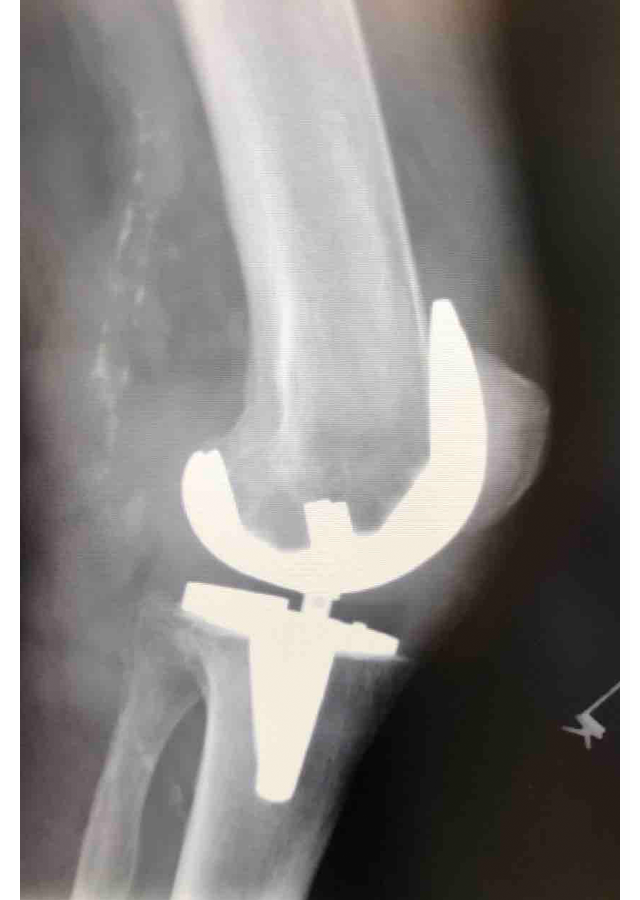

Csípő és térd ízületi betegségek protetizálása

Degeneratívtól, posttraumáson át veleszületett deformitásokig, revíziók, egyszerű és bonyolult helyzetek megoldása.